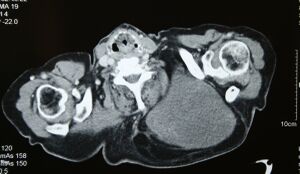

قد لا يكون التصوير بالموجات فوق الصوتية قادراً على التمييز بين الغرن الشحي والورم الشحمي الحميد، وبالتالي، فإن التصوير بالرنين المغناطيسي هو التصوير الأولي المفضل.[4]

MRI of myxoid liposarcoma of high grade, in left axillary region of 40 year old man. Highlighted by the white color. Horizontal section.